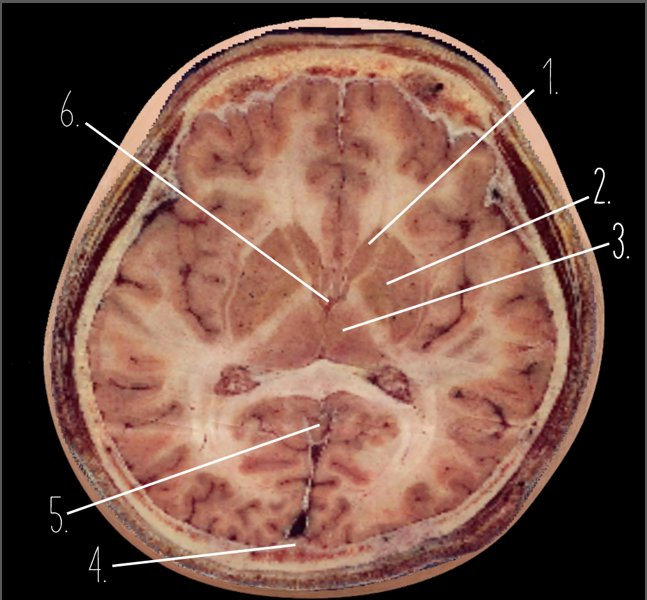

1?

Anterior Horn of the Lateral Ventricle

2?

Putamen

3?

Thalamus

4?

Internal Occipital Protuberance

5?

Cerebellar Vermis

6?

Third Ventricle